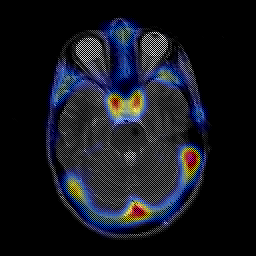

overlay -- Slice #8

[Home][Help][Clinical] Slice 8